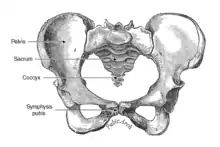

| Location of pubic symphysis | |